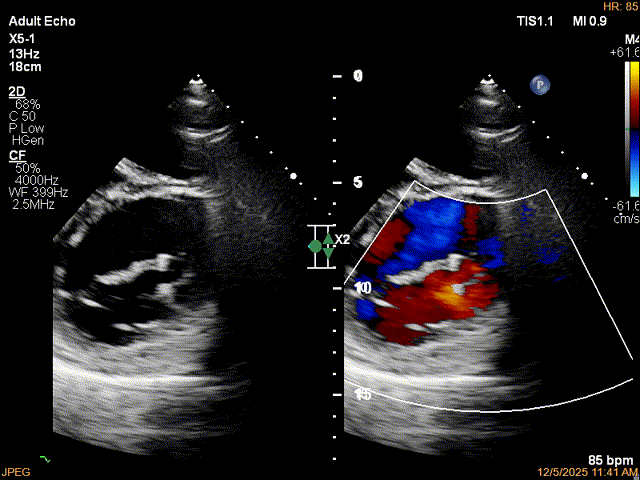

为了避免长时间TEE对食道造成损伤,术前即刻3D-TEE短时进一步明确二尖瓣病变相关解剖情况。

术前Bi-com

术前3D

术前3Dcolor

3D-TEE二尖瓣相关解剖学参数:后叶长度:22-25mm,前叶长度:31-34mm;瓣环AP径:47mm,ML径:48mm;瓣口面积:约7.8cm²;脱垂宽度:30mm,最大连枷间距:14mm。

四条肺静脉均可测及收缩期反向血流

术前即刻TEE进一步明确了二尖瓣反流的机制(DMR)及反流程度(5+),重点完善了病变区域二尖瓣解剖结构的评估,预估手术难点/影响手术效果的解剖结构为冗长的二尖瓣后叶(PML约25mm),宽大的脱垂(Flail Width约30mm),超大的连枷间距(Flail gap约14mm)。